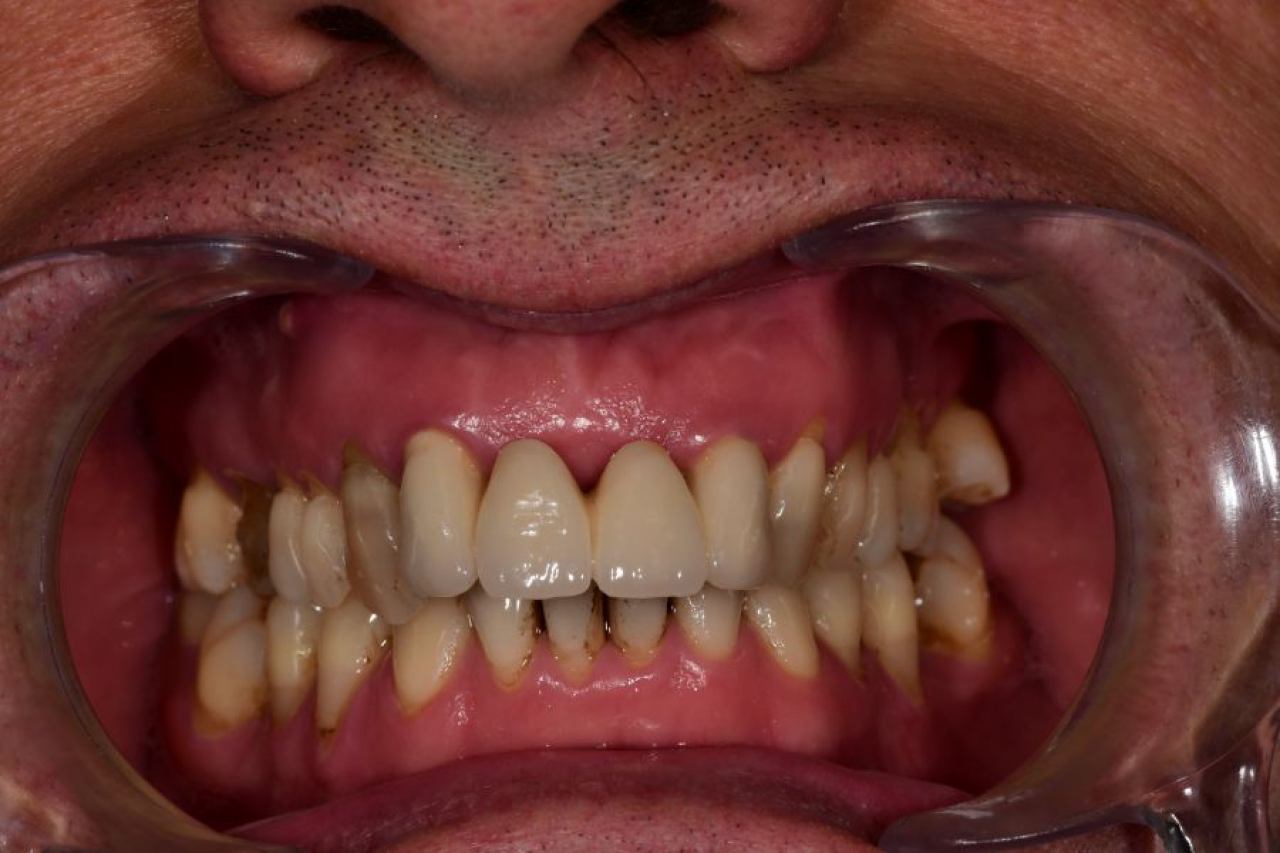

Implantologija - ugradnja dentalnih implantata

Dentalna implantologija je grana dentalne medicine koja objedinjuje znanje iz kirurgije, parodontologije i protetike i bavi se ugradnjom implantata u bezubu kost gornje ili donje čeljusti.

Marković Dental Clinic koristi najstariji, najistraživaniji i najkvalitetniji sustav dentalnih implantata Švedskog proizvođača Nobel Biocare.

All On 4 i All On 6 fiksni mostovi na 4-6 implantata, omogućavaju da se brzo, ekonomično i efikasno pacijentu od bezube čeljusti omogući mastikatorna i estetska funkcija.